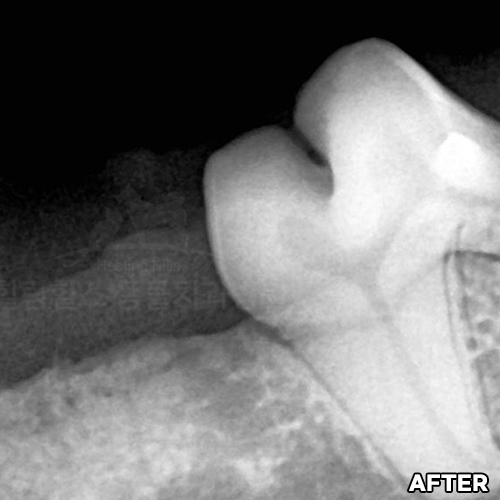

웰시코기의 아주 심한 파절치아를 강아지치과에서 수술하고 1년 뒤에도 잘 씹어요~!! - 동물치과 힐링힐스 -